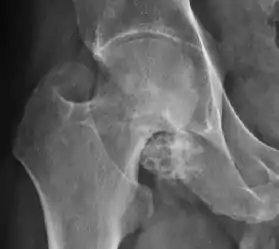

Synovial chondromatosis can be confidently diagnosed by X-ray when calcified cartilaginous chondromas are seen. However, other synovial proliferative processes, such as pigmented villonodular synovitis, require MRI for accurate diagnosis, although noncalcified synovitis can be suspected in radiographs by indirect signs, such as soft tissue swelling and/or erosions in the femoral head, femoral neck, or acetabulum (Figure 7).[1]

Figure 7:

Axial CT image of pigmented villonodular synovitis eroding the posterior cortex of the femoral neck.[1]

Sagittal T2* gradient echo image showing a posterior soft tissue mass with hypointense areas secondary to hemosiderin deposition.[1]

X-ray of synovial chondromatosis.[1]

CT of synovial chondromatosis.[1]